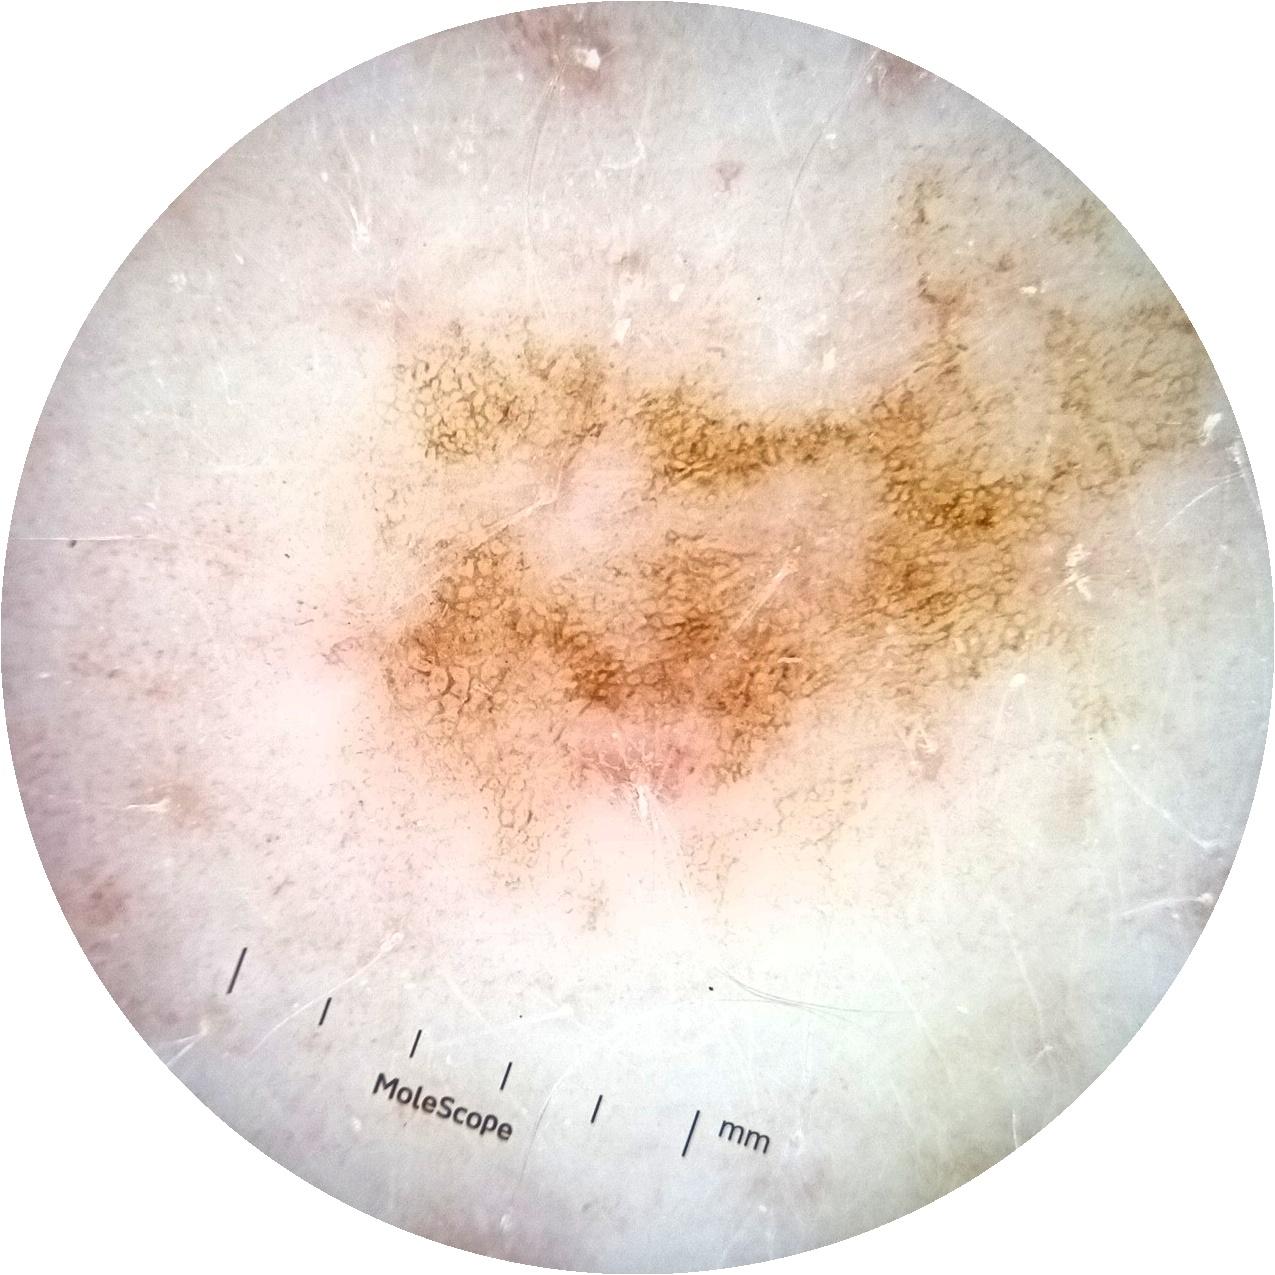

acquisition_day 135

age_approx 65

anatom_site_1 Upper extremity

diagnosis_1 Benign

diagnosis_confirm_type single image expert consensus

fitzpatrick_skin_type I

image_type dermoscopic